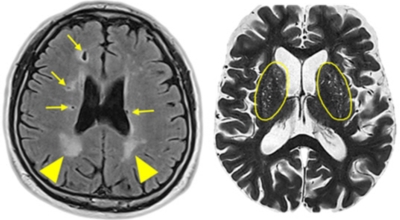

뇌경색의 경색이란 허혈성 괴사를 말해요. 여기서 허혈이란 혈관이 막히는 것을 말하고 괴사는 말 그대로 일부가 죽는 것을 말하는데 뇌경색의 경우 뇌의 혈관이 막혀 뇌세포 일부가 죽는 걸 의미해요. 뇌혈관이 막혔다 해서 혈액 공급이 안되는것은 또 아니에요.

막힌 혈관으로도 혈액이 공급되긴 하나 혈관이 막혀있어 혈액을 보내긴 하나 제대로 흐르지 못하고 혈액이 쌓이고 축적되어 물풍선에 물이 꽉 차서 터지듯 뇌혈관이 터지는 경우가 일어날 수 있는데 이를 뇌출혈 이라고 해요. 물론 외상으로 인한 뇌출혈도 있지만 이처럼 뇌경색으로 인해 혈관이 막혀 터지는 경우도 있어요.

뇌경색의 가장 흔한 원인은 고혈압, 당뇨, 고지혈증 등으로 인해 뇌에 혈액을 공급하는 혈관에 뇌혈류가 차단되는 경우와 그 밖에심장 부정맥, 심근경색의 후유증 등으로 인해서 심장에 혈액이 응고된 상태가 되고 이 혈전이 혈류를 따라 이동하다가 뇌혈관을 막아 뇌졸중이 나타나는 경우도 있어요.